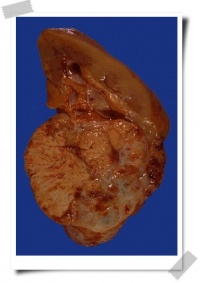

巨检:肿瘤外观为不规则圆形或椭圆形肿块,有一层纤维包摸;血供丰富,血管怒张,有充血及出血区。肿瘤的颜色与血管多少、癌细胞内脂质含量以及出血、坏死等因素有关,一般说来,生长活跃区为白色,透明细胞呈黄色,颗料细胞或未分化细胞呈灰白色。暗红色或红色部位分别为陈旧或新鲜出血区,常有囊性变、中心坏死、血肿或不规则钙化灶。

肾癌常为单侧单病灶,左右侧发病数相似肾癌多数为圆形,大小十分悬殊。肿瘤无组织学包膜,但有被压迫的肾实质和纤维组织行成的假包膜,少数为均匀的黄色或棕色,多数体有出血、坏死、纤维化斑块,出血坏死可形成囊性,本身为乳头状囊腺癌。肿瘤可破坏全部肾脏,并可侵犯邻近脂肪、肌肉组织、血管,淋巴管等,肾周围筋膜是防止局部扩散的一层屏障。肾癌易向静脉内扩展形成癌栓,可伸延进入肾静脉、下腔静脉。远处转移常见为肺、脑、骨等。